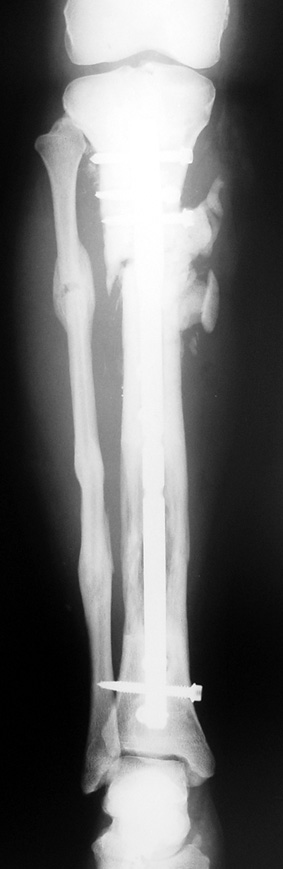

Uygun radikal debridman tüm nekrotik kemik ve yumuşak dokuların çıkartılmasını gerektirir, ve sıklıkla uzuvda instabiliteye neden olur. Kalan kemik ve yumuşak doku defektinin bir şekilde fiksasyonu ve rekonstrüksiyonu gereklidir. İlizarov’un ortaya koyduğu distraksiyon osteogenezi yöntemi, kaynamanın elde edilmesi, deformitenin düzeltilmesi, bacak boy eşitsizliğinin giderilmesi ve segmental defektlerin rekonstrükte edilmesi için başarıyla kullanılmaktadır.

Eksternal fiksatör ile geçen süre (eksternal fiksasyon indeksi), gereken distraksiyon miktarına bağlıdır ve bu süre boyunca bazı komplikasyonlarla karşılaşılabilir. Distraksiyon dönemi sona erdikten sonra, distraksiyon süresinin iki katını aşan konsolidasyon döneminde hastalar eksternal fiksatörü zorlukla tolere edebilirler. Yeterli konsolidasyon sağlanmadan eksternal fiksatör çıkartılırsa ise kırıklar, deformite ve kısalık oluşabilir. Hastanın fiksatör ile birlikte geçirdiği sürenin azaltılması ve böylece hasta konforunun ve aktivite düzeyinin arttırılması için intramedüller çivi üzerinden uzatma yöntemi uygulanmaktadır. Bu yöntemde distraksiyon dönemi sona erdiğinde kemiğin içindeki çivi statik olarak kilitlenmekte ve eksternal fiksatör çıkartılmaktadır. Stabilizasyon intramedüller çivi tarafından sağlandıktan sonra konsolidasyon dönemi gerçekleşmektedir. Bu şekilde hem eksternal fiksatörün uzun süre kalmasından hem de erken çıkartılmasından kaynaklanan komplikasyonların önüne geçilmektedir.